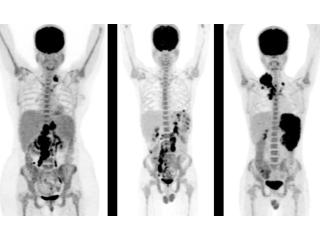

Picture This offers advanced PET CT Scan in Mumbai, combining positron emission tomography with computed tomography for unparalleled diagnostic accuracy. Our cutting-edge technology enables early disease detection, effective staging, and better treatment planning across oncology, cardiology, and neurology. Backed by skilled radiologists and global diagnostic standards, we provide precise imaging for patients worldwide. We prioritize patient safety and comfort, with radiation exposure kept minimal. Choosing the right diagnostic partner can transform outcomes. Book your PET CT Scan in Mumbai with Picture This today for unmatched accuracy.